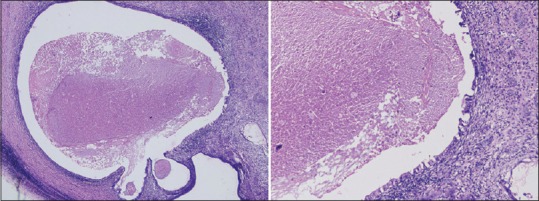

A 29-year-old male patient, with no prior known medical or dermatological comorbidities or any drug allergy, was diagnosed as a case of Stage IIIB testicular cancer. Contrast-enhanced computed tomography chest, and abdomen was suggestive of the lobulated lesion in paraaortic region with multiple bilateral lung nodules, mediastinal, and hilar lymphadenopathy [Figure 1]. Preoperative tumor marker analysis revealed serum alpha-feto protein level 12,100 ng/ml, serum beta human chorionic gonadotropin (HCG) level 2.39 mIU/ml, and serum lactate dehydrogenase (LDH) level 819 U/L. He underwent right high inguinal orchiectomy in May 2015. Final histopathology report was suggestive of mature cyctic teratoma of right testis with associated features of intratubular germ cell neoplasia [Figure 2]. Postoperative tumor marker analysis revealed serum alpha-feto protein level 126 ng/ml, serum beta-HCG level 2.39 mIU/ml and serum LDH level 292 U/L. Patients pulmonary and renal function tests were normal. He was started on bleomycin (30 units on days 1, 8, and15), etoposide (100 mg/m2 on day 1–5), and cisplatin (20 mg/m2 on day 1–5) based chemotherapy (BEP chemotherapy) as per our institutional protocol. However, after 3 cycles of chemotherapy, the patient started complaining of pruritic linear rashes which patient noticed first over the trunk and then gradually increased to involved skin over the chest, back, shoulder, and bilateral upper and lower limbs [Figure 3]. On physical examination, linear and streaked pigmentation were seen on bilateral upper limbs, lower limbs, and over chest and back. No other skin lesions were noted. There was no mucosal involvement or systemic upset. A clinical diagnosis of bleomycin-induced flagellate rash and postinflammatory pigmentation was considered. Routine laboratory investigations, including liver and renal function tests, were normal. Bleomycin was withheld from subsequent chemotherapy cycles, and the patient was prescribed betamethasone dipropionate ointment for local application twice a day for 2 weeks. On subsequent follow ups, the itching sensation was reduced was mild hyperpigmentation remained [Figure 4].

| Figure 1:Histopathology slides showing mature cystic teratoma with Intratubular germ cell neoplasia

| Figure 1:Histopathology slides showing mature cystic teratoma with Intratubular germ cell neoplasia